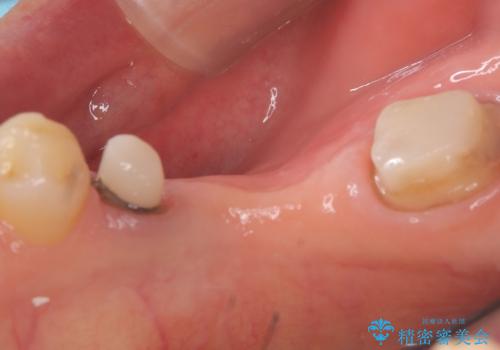

- 主訴:つい先日入れたセラミック(ジルコニア)ブリッジが奥歯部分で割れた。いつも同じ場所で壊れる。これで3度目。

セラミックに比べ、割れづらい金属(ゴールドでのブリッジのやり替えとなりました。

セラミックに比べ、破折リスクの少ない金属を使用したブリッジでのやり替えとなりました。

両支台歯が失活歯のため、どちらかもしくは両方の歯が破折した際、再度ブリッジを除去した治療が必要になるリスクとインプラント治療のご提案もさせていただきましたが、ブリッジでの治療を希望されました。

右下5番は支台歯CR築造を行っています。